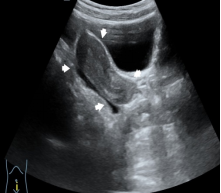

发育的子宫

(白色箭头所指)

发育的卵巢,可见多个直径≥4 mm 的卵泡